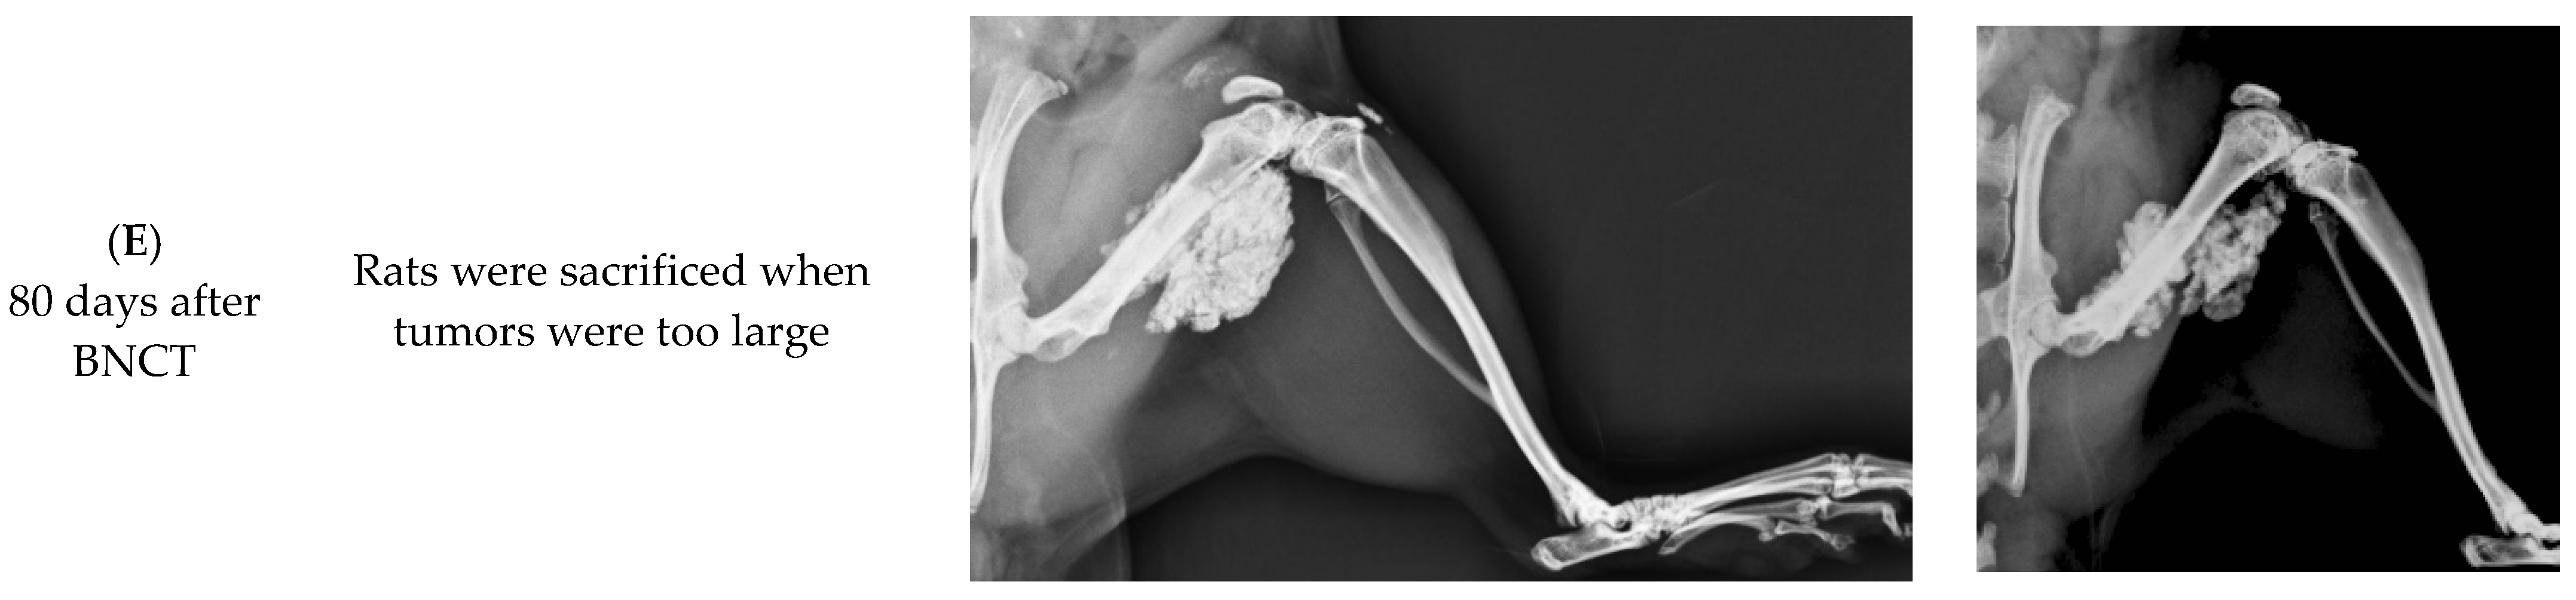

3.5. Relationship between BA Retention and Calcification in OS Tissue